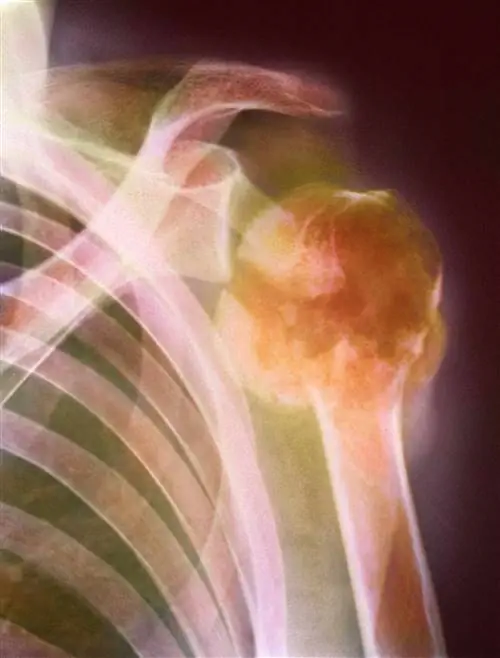

Красный костный мозг находится в основном в плоских костях, таких как бедро, ребра, тазовые кости, позвоночник и плечевая кость - это области, которые чаще всего поражаются множественной миеломой.

Накопление клеток миеломы может вызвать локальные опухоли в костях, называемые плазмоцитомами. Напротив, при множественной миеломе накопление плазматических клеток затрагивает костный мозг нескольких костей и может негативно влиять на другие здоровые иммунные клетки, поскольку мешает их способности адекватно бороться с инфекцией. В свою очередь, это может привести к нехватке эритроцитов (анемия), а также к нехватке здоровых лейкоцитов (лейкопения).

• Переломы костей (вследствие инвазии кости плазмоклеточными опухолями)